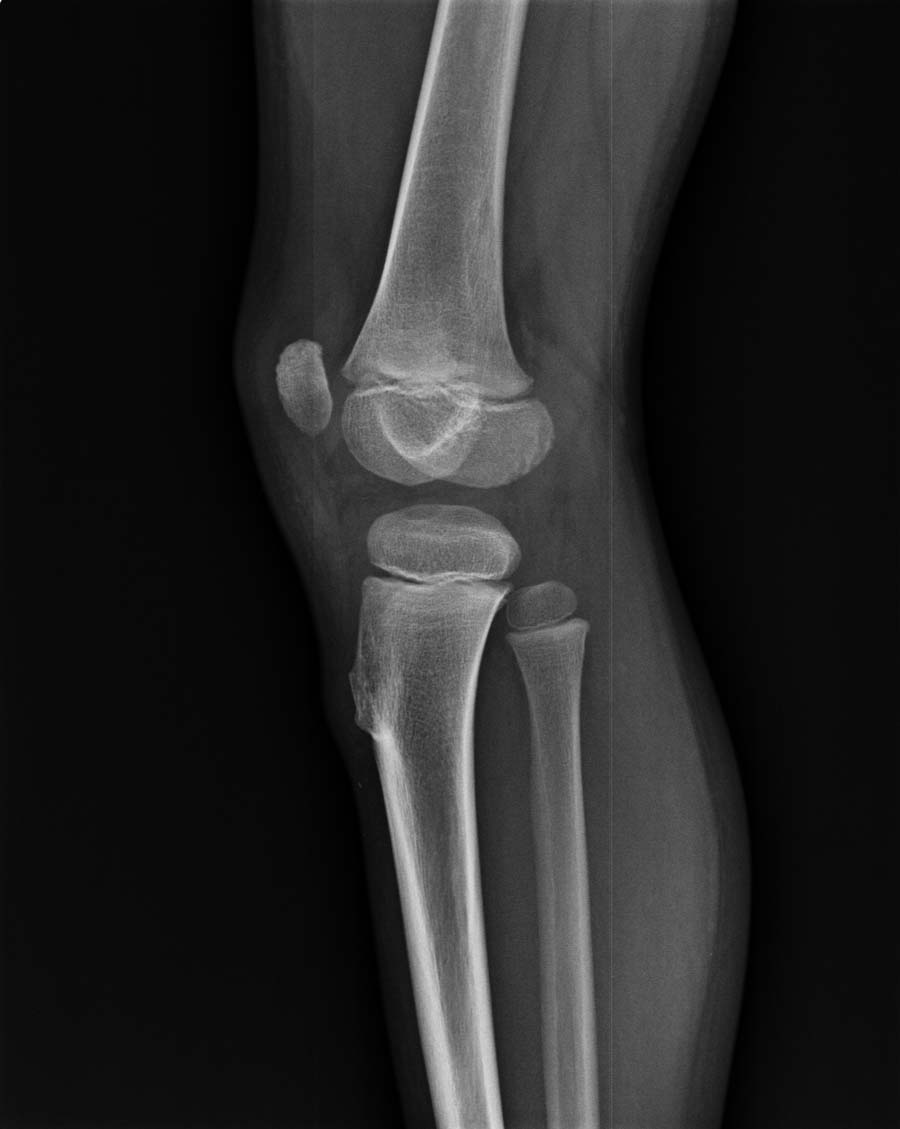

以下是引用杀毒软件在2008-5-26 22:37:00的发言:[br]右胫骨纤维性骨皮质缺损可能性大

以下是引用蚂蚁在2008-5-26 23:01:00的发言:[br]宽基底骨软骨瘤!